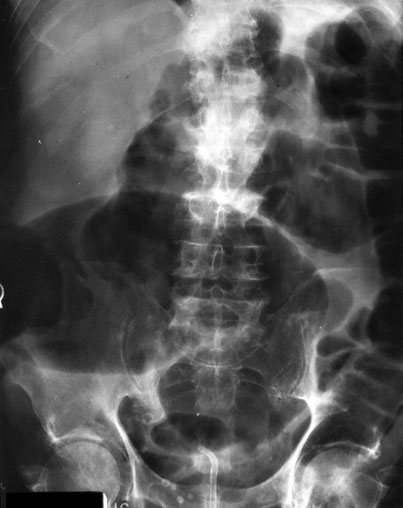

A 62-year-old woman is brought to the emergency department because of a 1-day history of severe abdominal pain. Two weeks ago, she began taking amoxicillin-clavulanate for a respiratory tract infection. One week later, she had fever, bloody diarrhea, and mild abdominal cramps. She discontinued the amoxicillin-clavulanate, and began taking over-the-counter omeprazole and loperamide for relief of the symptoms. Her symptoms have worsened, and she now rates her abdominal pain as a 9 on a 10-point scale. She has a 6-year history of type 2 diabetes mellitus controlled with diet. She was not taking any medications prior to the amoxicillin-clavulanate. She appears acutely ill. She is 165 cm (5 ft 5 in) tall and weighs 104 kg (230 lb); BMI is 38 kg/m2. Her temperature is 38.6°C (101.5°F), pulse is 110/min, respirations are 14/min, and blood pressure is 112/76 mm Hg. Abdominal examination shows distention and diffuse tenderness to palpation and voluntary guarding. The remainder of the examination shows no abnormalities. Her leukocyte count is 28,000/mm3. Test of the stool for Clostridium difficile toxin A is positive. An abdominal x-ray is shown. Which of the following is the most likely cause of this patient’s condition?